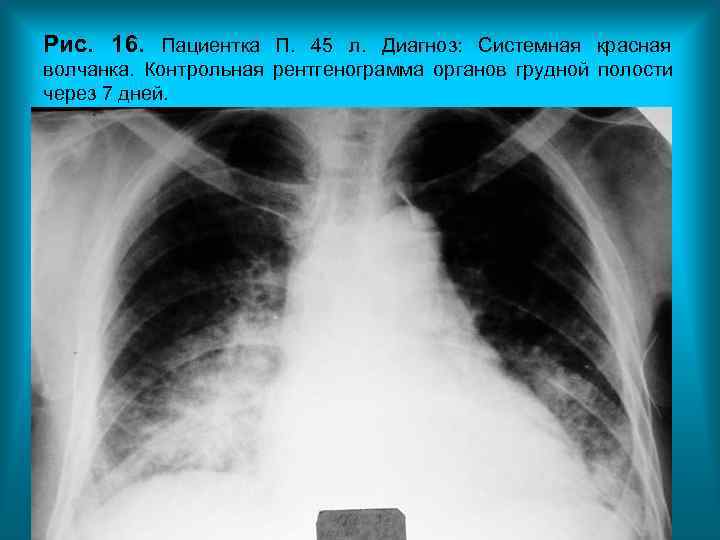

Рис. 16. Пациентка П. 45 л. Диагноз: Системная красная волчанка. Контрольная рентгенограмма органов грудной полости через 7 дней.